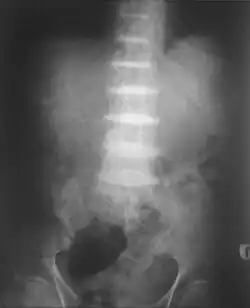

After the age of 30, people begin to develop pain in the weight-bearing joints of the spine, hips, and knees. The pain can be severe to the point that interferes with activities of daily living and may affect the ability to work. Joint-replacement surgery (hip and shoulder) is often necessary at a relatively young age.[1] In the longer term, the involvement of the spinal joints leads to reduced movement of the rib cage and can affect breathing.[1] Bone mineral density may be affected, increasing the risk of bone fractures, and rupture of tendons and muscles may occur.[1]